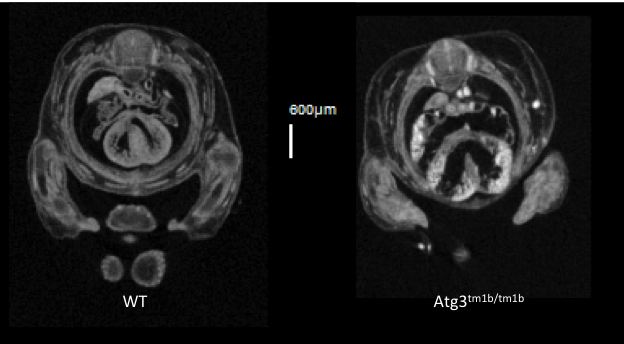

Atg3tm1b(EUCOMM)Hmgu

Atg3 is an E2-like protein-conjugating enzyme involved in autophagy broadly expressed during development and in the adult.

Atg3 mutants show complete preweaning lethality with no homozygous pups observed, but they are viable at least until E14.5. Micro-computed tomography (microCT) imaging at E14.5 revealed homozygous mutant fetuses had cardiovascular abnormalities such as ventral septum defects (VSD), thick atrio-ventricular valves and a thin myocardium, as well as an enlarged umbilical vein.